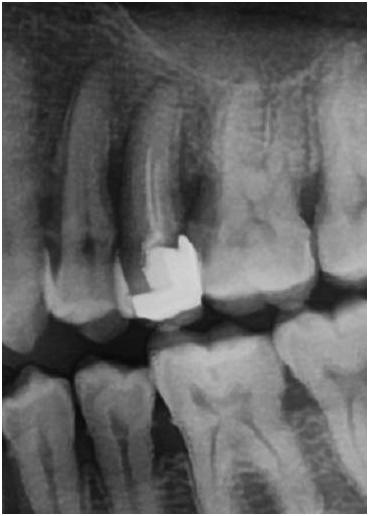

再来看看做得差的:

上面这位大哥说他做了根管的

片子显示根管里什么都没有┓(;´_`)┏

这位姐姐也说做了根管的

但是根管里面就细细的两根牙胶尖,根本没有填满